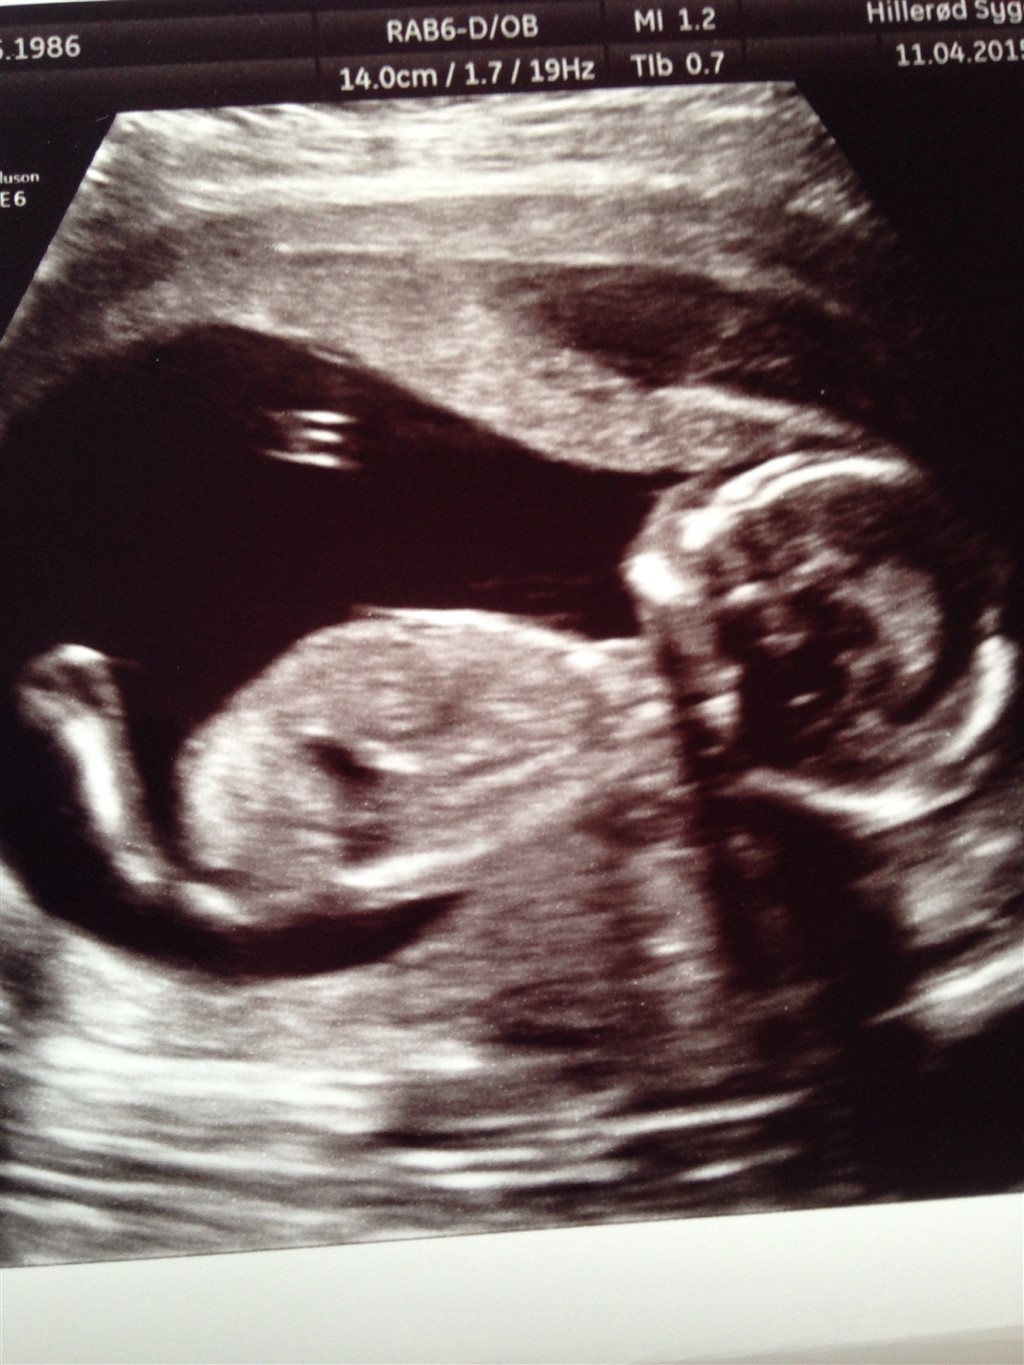

Jeg kan ikke forestille mig den er tømt, da jeg ikke har blødt meget gammelt, bare lidt hver dag i 14 dage. Nu er det holdt op, og håber den ikke vokser. Den var så stor at det tydeligt sås på billederne over babys hoved...

Vedhæftede fotos (klik for at se i fuld størrelse)